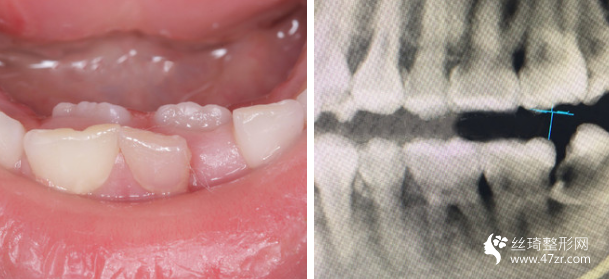

3.武漢伽美醫(yī)療美容醫(yī)院譚頔牙周病、烤瓷、牙美容行業(yè)專家案例展示

我的牙齒其實(shí)問題不大,但是下面兩個牙齒被擠的歪了出來,而且我 一直覺得我的嘴有點(diǎn)往外凸出,所以一直都有矯正的想法,朋友在他 們家做的貼面,推薦給我說薇琳醫(yī)生很專業(yè)的,所以我也就過來了。 首先做了檢測,然后設(shè)計了方案,取模,然后根據(jù)自己的牙齒情況制 定矯正器。 耐心等待我矯正器的到來。

很感謝我遇到了不錯的醫(yī)生,在這方面臨床經(jīng)驗(yàn)比較豐富,醫(yī)生說我的矯治過程進(jìn)展的較為順利,矯正速度真的是較為快呢,牙齒不齊整體也在調(diào)整牙齒咬合狀態(tài)了。

現(xiàn)在笑的時候更加自信了,所以牙弄齊了以后我打算在做個美白,平時抽煙牙齒也很黃